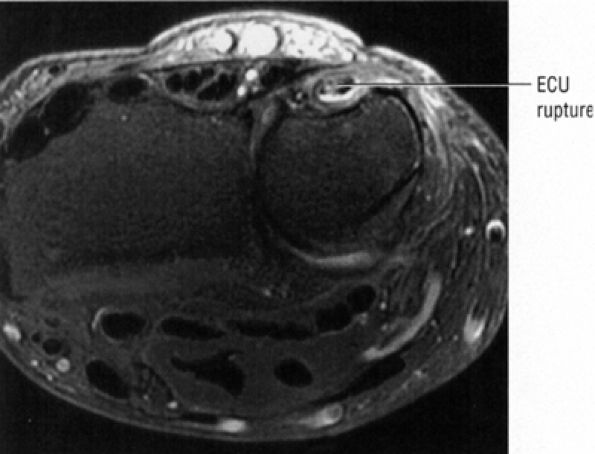

FIGURE 10.15 ● EXTENSOR CARPI ULNARIS The extensor carpi ulnaris tendon extends and adducts the wrist. It is commonly affected in tendinosis and tenosynovitis as it passes through the groove on the distal ulna. Subluxation of the extensor carpi ulnaris can also occur at this location related to disruption or insufficiency of the ligament that covers the tendon in this groove. The extensor carpi ulnaris tendon subsheath is a component of the triangular fibrocartilage complex.

|